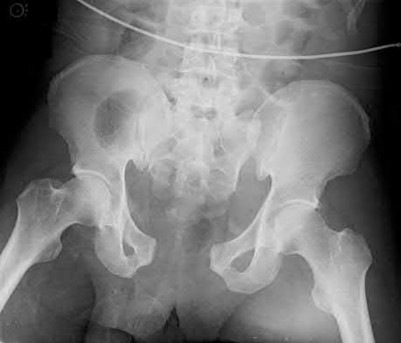

2. # A 35-year-old woman is involved in a head-on collision while driving. Initial radiographs are shown in Figures 8a and 8b. Injury to what vessel increases the risk for osteonecrosis of the injured bone?

5. Artery of the tarsal sinus Corrent answer: 4

The patient has a Hawkins type III talar neck fracture-dislocation with a risk of osteonecrosis ranging from 69% to 100%. Anatomic studies have shown that the artery of the tarsal canal supplies the lateral two thirds of the talar body.

The other vessels listed provide no significant contribution to the talus.